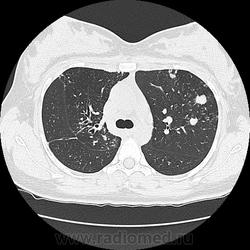

Ага, сначала вот эта с каверной пришла 12.05, а потом с туберкуломами 19.05 с интервалом в неделю, закон парных случаев, обе только родили, род.дом в панике, я в шоке

В том то и дело, что анамнез скудный, жалоб нет или врала, жила себе поживала девушка, забеременела, родила, а в правом легком "дырка".

Очень хочется "скиалогической" динамики, хоть КТ, хоть "классику"...

А вот это не обещаю, но ежели пациентка придет на контроль в наше учреждение, то обязательно дополню к данному случаю. Хотя есть вариант позвонить в ПТД и выпросить у них контрольные снимки, на досуге озадачусь.